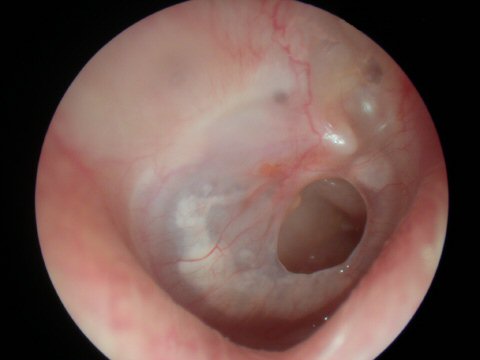

Notice the different shades of color yet the eardrum still remains an opaque translucent appearance in all the pictures

Acute Infection with bulging of the tympanic membrane due to pressure from purulence (pus) behind it. The last picture reveals an ear tube that has gotten prematurely blocked and the ear is once again infected.